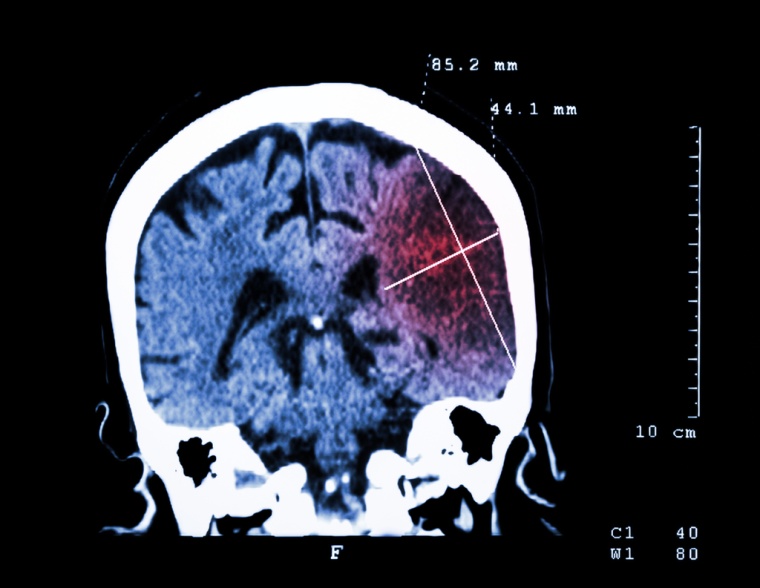

Der Schlaganfall ist in Deutschland nach Herz- und Krebserkrankungen die dritthäufigste Todesursache und die häufigste Ursache für bleibende Behinderungen im Erwachsenenalter. Rund 200.000 Männer und Frauen sind jährlich davon neu betroffen, etwa 66.000 erleiden zum wiederholten Mal einen Schlaganfall. Die häufigste Form ist der ischämische Schlaganfall: ein Hirninfarkt, der durch eine Minderdurchblutung des Gehirns ausgelöst wird, häufig verursacht durch ein Blutgerinnsel.